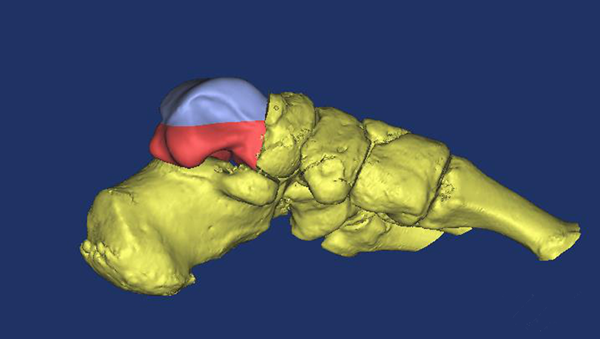

这位43岁的女性患者因不幸遭遇车祸,造成距骨粉碎骨折、脱出,导致左踝关节开放性脱位并距骨体缺损,踝关节活动受限,属罕见的病例。西安高新医院特邀我院骨二科贺西京教授会诊。贺西京教授根据患者病情,结合目前国际先进的3D打印技术,通过诊断,决定采用3D打印定制个体化距骨假体植入方案。由于患者左距骨丢失,贺西京教授团队通过患者右脚CT数据信息,镜像后的三维数字模型为患者“私人定制”量身定做左脚距骨,实施假体置入术,手术由贺西京教授亲自主刀,高新医院骨一科医生配合下,经过两个小时手术,成功将3D打印好的距骨精确无误的植入患者缺失部位,手术获得成功。

据悉,数字化、精准化、个性化的3D打印新技术由于已在术前把患者的数据做了精确的测量,误差小于0.01毫米,手术変得更加精准,创伤更小,出血更少,手术时间更短。此手术的成功实施得到阳光网、CCTV网络版等媒体报道。